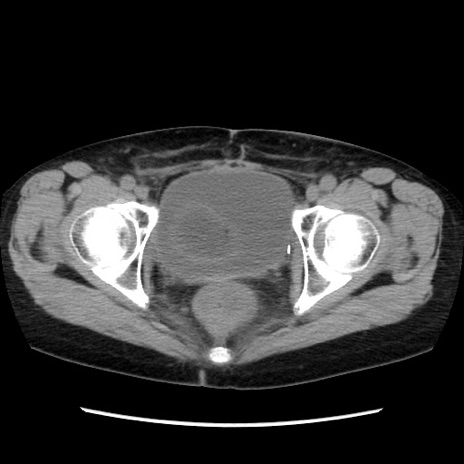

症例32(横断像)

【症例】40歳代 女性

【主訴】上腹部痛、嘔気・嘔吐

【現病歴】約9時間前頃から急に上腹部痛、嘔気、嘔吐が出現。改善しないため救急要請。

【既往歴】子宮頚癌(広汎子宮全摘術、放射線療法)、腸閉塞

【身体所見】腹部:平坦、軟、腸雑音亢進、上腹部を中心に腹部全体に圧痛あり。

【データ】WBC 8400、CRP 0.03